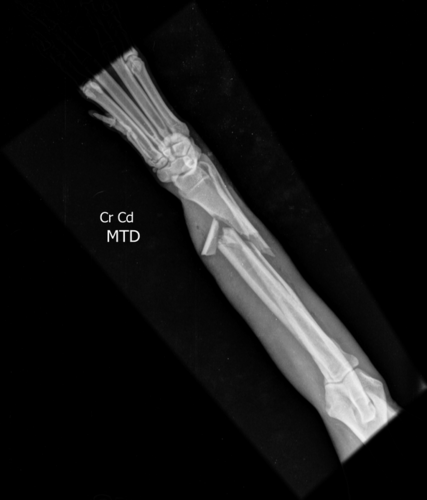

Infelizmente no dia 15/04 ele foi vítima de um atropelamento, como consequência teve fratura no maxilar e na patinha, e também está com processo inflamatório no pulmão!Os tutores não tem condições para arcar com todos os gastos, porque além disso tudo, o dono/companheiro do Campeão é portador do Autismo, e ele precisa URGENTEMENTE do seu melhor amigo em casa novamente!A cirurgia das fraturas está no valor de $3000. Além disso ele precisa de internação e controle com medicação no pós cirurgico.